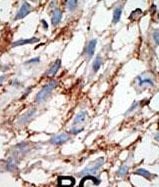

IHC (Immunohiostchemistry)

(Formalin-fixed and paraffin-embedded human cancer tissue reacted with the primary antibody, which was peroxidase-conjugated to the secondary antibody, followed by DAB staining. This data demonstrates the use of this antibody for immunohistochemistry; clinical relevance has not been evaluated. BC = breast carcinoma; HC = hepatocarcinoma.)